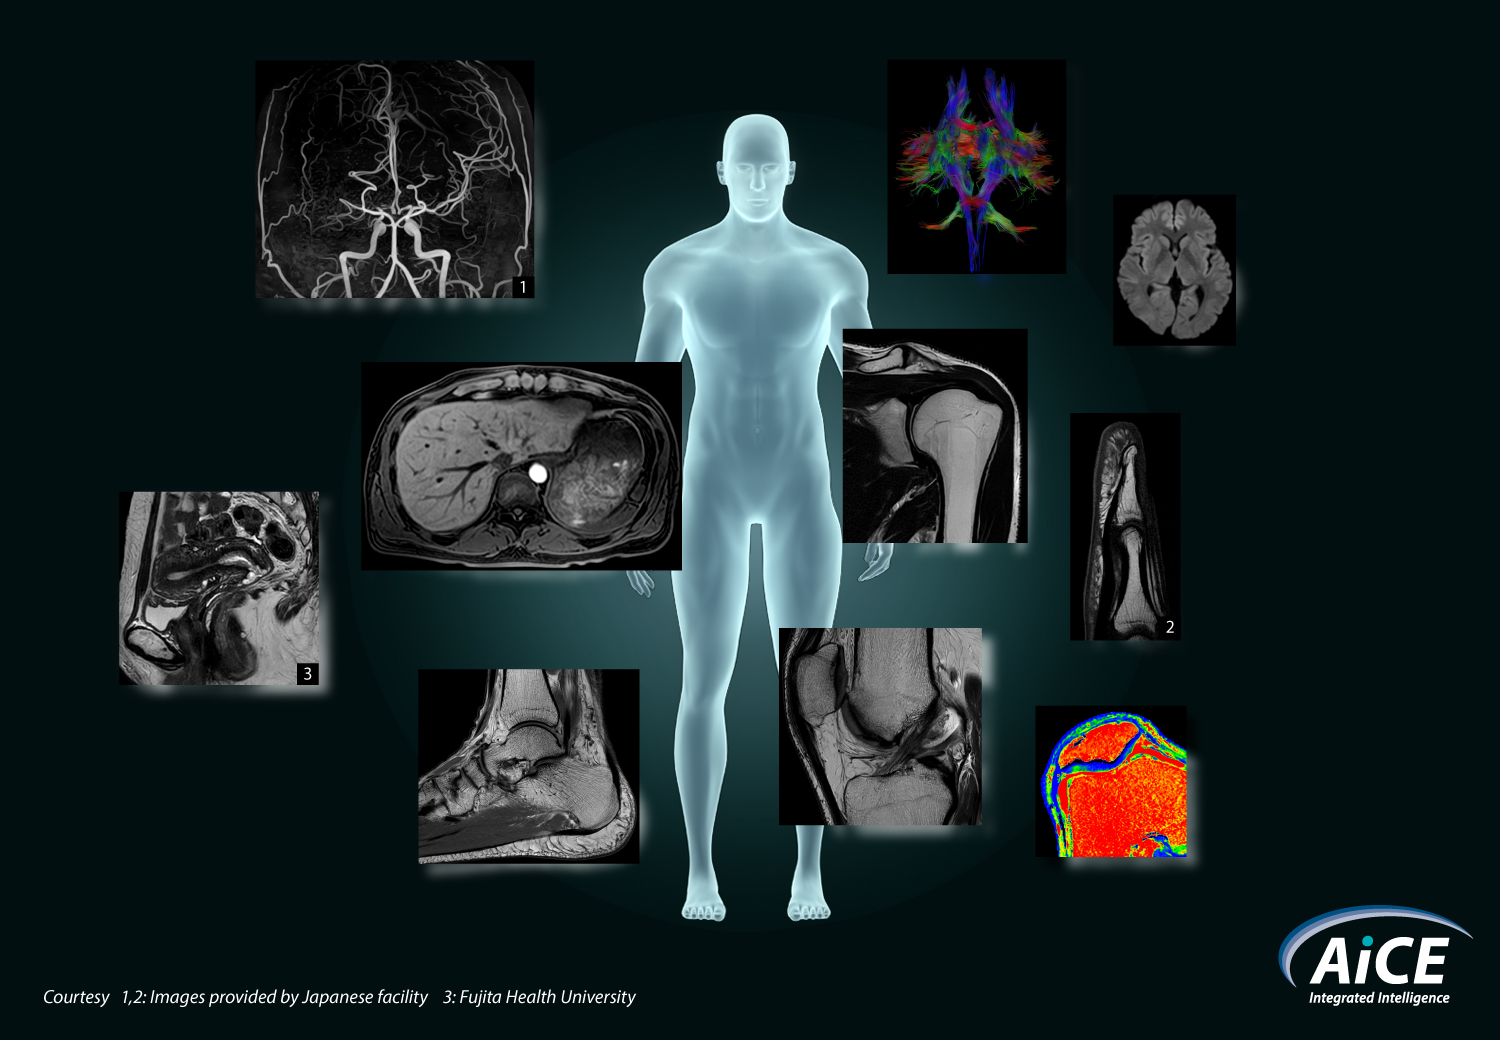

Advanced intelligent Clear-IQ Engine (AiCE)

AiCE có thể áp dụng cho tất cả các vùng cơ thể và hầu hết tất cả các trình tự.

AiCE đã mở rộng các giải pháp chụp ảnh cơ thể để cung cấp thông tin nhanh chóng, chính xác và cần thiết nhằm giúp bạn chăm sóc bệnh nhân tốt hơn